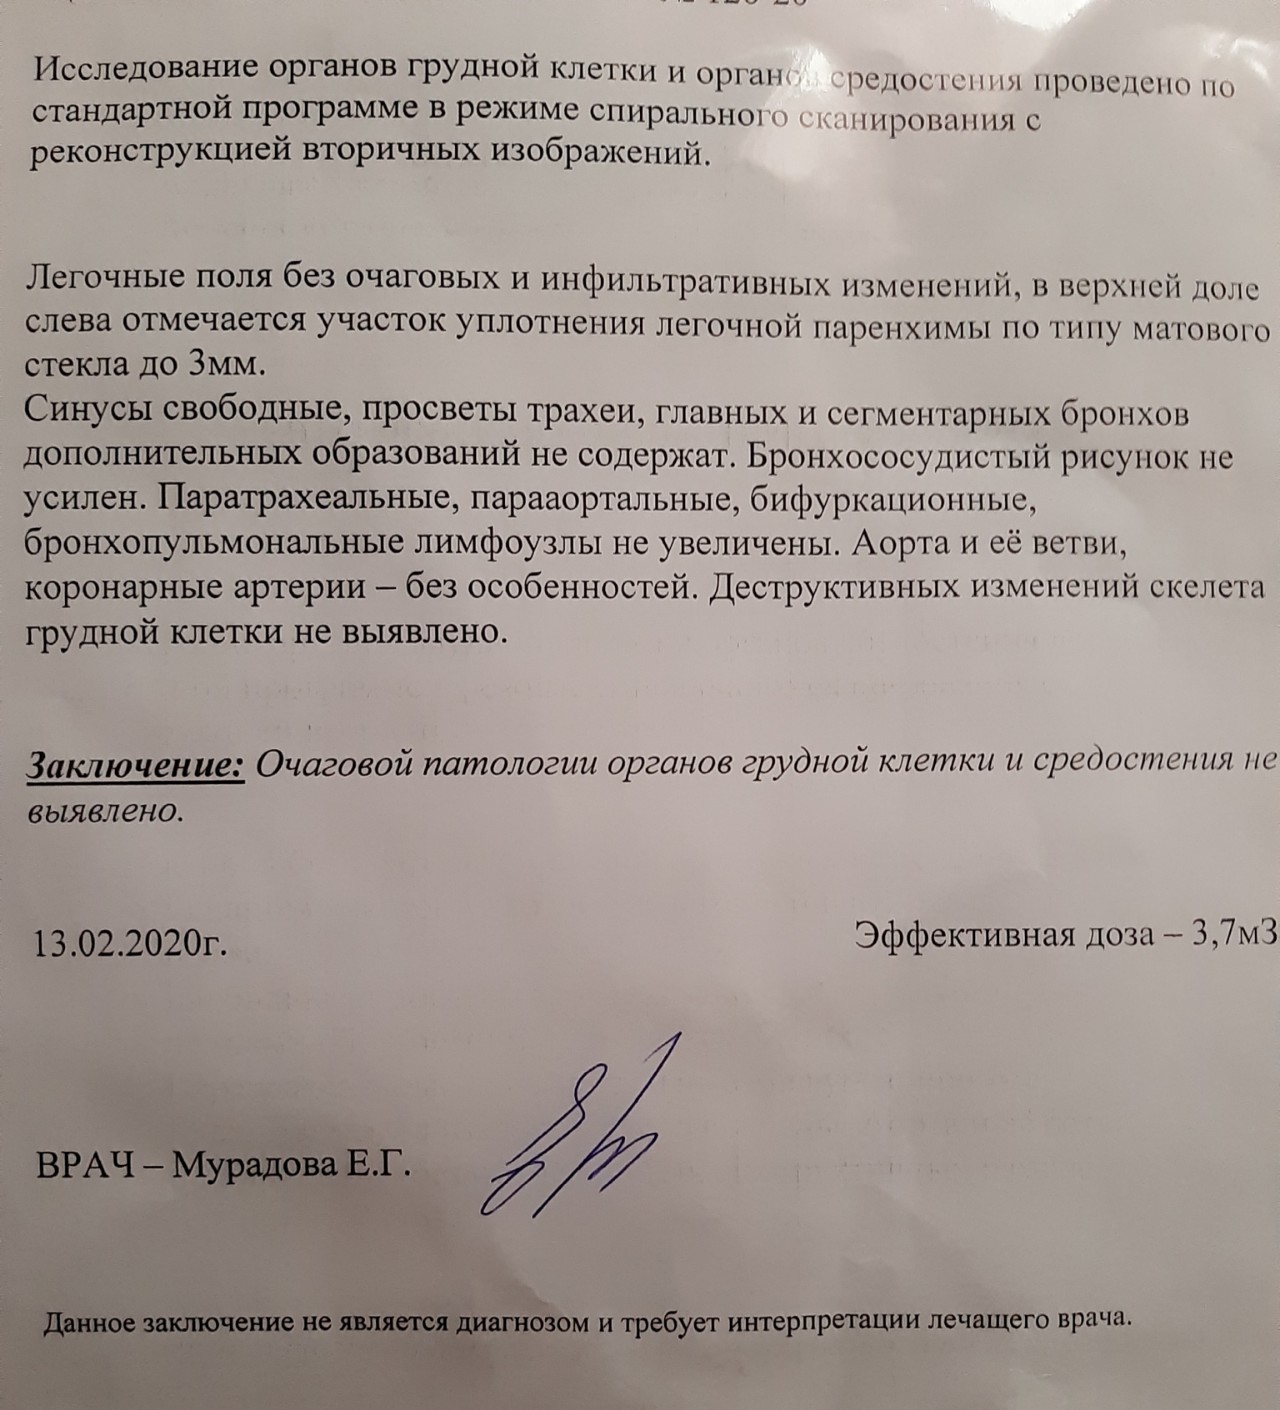

Фотографии, демонстрирующие обнаруженное усиление легочного рисунка

Раздел: Фотодневник открытий